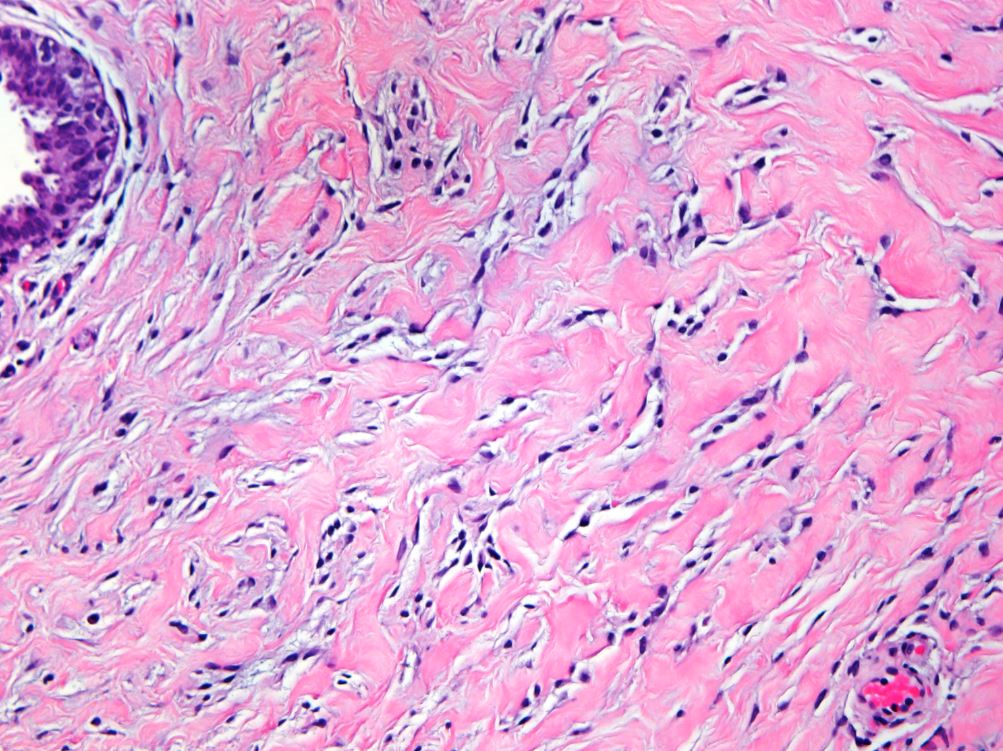

A 64 year-old man with history of clear cell renal cell carcinoma s/p nephrectomy (2021) presents with scrotal pain and firmness. Ultrasound reveals a 2 cm solid lesion. Serum tumor markers (hCG and AFP) were normal. The tumor was negative for SALL4, OCT3/4, AFP, and showed focal patchy positivity for pancytokeratin (focal). PAX8 was weakly positive. Additional stains are displayed in the pictures.